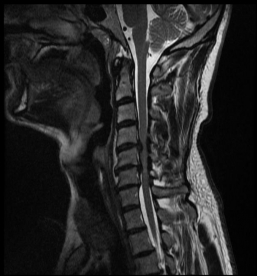

MRI with lateral reconstruction of the lumbar spine. The hourglass-like narrowing of the spinal canal can be seen at two heights.